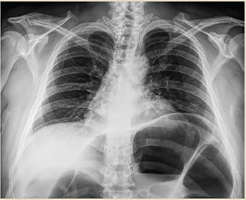

Paciente del sexo masculino, de 79 años, inició su padecimiento actual con estreñimiento de 10 días de evolución; se agrega náusea, vómito, distensión y dolor abdominal. Antecedentes relevantes: diabetes mellitus tipo 2 en control, negó antecedentes quirúrgicos; antecedentes de trauma abdominal cerrado durante la infancia posterior al cual presentó varios cuadros de distensión, y dolor abdominal difuso y estreñimiento crónico. A la exploración física dirigida se observó distensión abdominal, silencio abdominal, se palparon impresiones aparentemente de asas intestinales predominantemente en flanco e hipocondrio izquierdos; doloroso a la palpación profunda, con abdomen en tabla, signo de rebote no valorable, hipertimpanismo a la percusión. Estudios paraclínicos reportaron acidosis metabólica leve con déficit de base. Las radiografías de tórax y abdomen evidenciaron distensión importante del colon transverso hasta el ángulo esplénico e incremento del patrón de distribución aérea, así como colon sigmoides dilatado y desplazamiento e interposición de asas sobre colon ascendente y ángulo hepático con niveles hidroaéreos (figuras 6 y 7). Se integró diagnóstico de probable megacolon secundario a vólvulo intestinal complicado, con datos de peritonitis e isquemia intestinal. Se indicó laparotomía exploratoria de urgencia; como hallazgos quirúrgicos se obtuvieron colon descendente y sigmoides distendidos, diámetro máximo de 20 cm y 100 cm de longitud (figura 8), laxitud marcada de sus medios de fijación, vólvulo a nivel de transición de colon descendente y sigmoides, así como múltiples adherencias en el trayecto del colon transverso, descendente y sigmoides (figura 9). Se realizó procedimiento de Hartmann con colostomía de colon transverso.

Figura 6 PA de tórax. Distensión importante de colon transverso y ángulo esplénico, incremento del patrón de distribución aérea, desplazamiento de hemidiafragma y hemitórax izquierdo